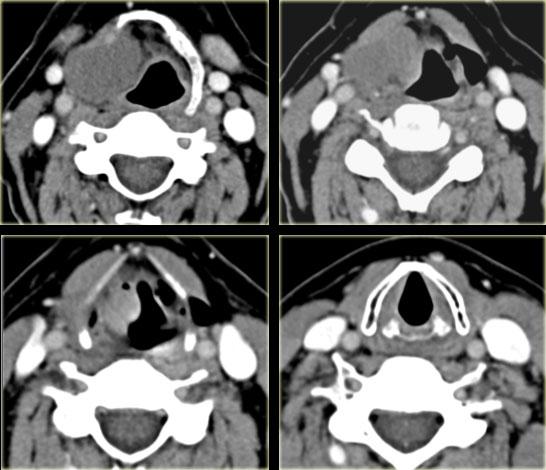

Bên trái là các lát cắt liên tiếp theo hướng từ trên xuống dưới ở mức thanh quản.

Hãy nghiên cứu ca này, khá tương tự với một ca đã được thảo luận trước đó, sau đó tiếp tục đọc.

Khối có tỷ trọng dịch ở bên phải tại mức thanh quản trên thanh môn, tức là túi thoát vị thanh quản.

Có một thành phần nhỏ ngoài thanh quản.

Phía dưới túi thoát vị thanh quản này là một khối u nhỏ ngấm thuốc ở buồng thanh quản (mũi tên đỏ).

Sinh thiết xác nhận ung thư biểu mô tế bào vảy. - Bên trái có một túi thoát vị thanh quản chứa khí (mũi tên xanh).

- Dây thanh âm (v) bình thường.